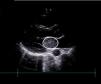

The findings of initial tests, including bloodwork, toxicology, head CT and lumbar puncture, were unremarkable. The patient then developed right-sided hemiparesis with homonymous hemianopia and aphasia (score of 9 on the Pediatric NIH Stroke Scale [PedNIHSS]). A cerebral CT angiogram revealed an embolic ischemic stroke resulting from the occlusion of the M2 segment of the left middle cerebral artery. The etiological evaluation revealed a large left atrial mass (Fig. 1), which was surgically excised and confirmed as a myxoma in the histological analysis.